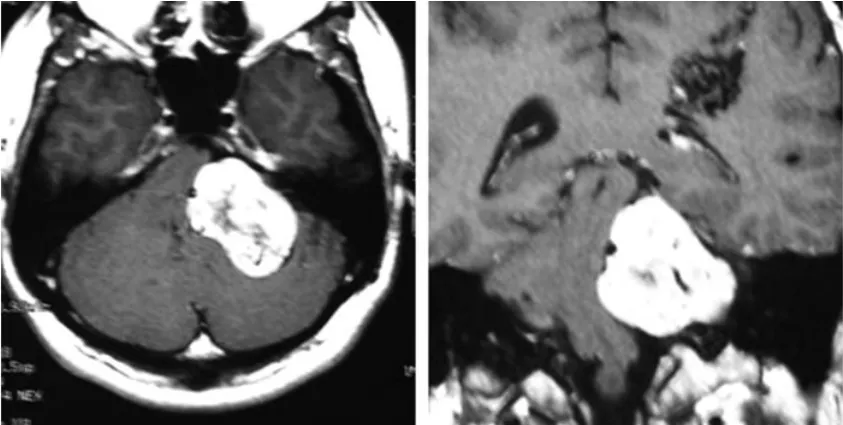

一位27岁男性因左侧面部麻木及平衡障碍就诊。影像学检查显示左侧桥小脑角区存在一直径约4.5厘米的占位性病变,影像特征符合听神经瘤表现,肿瘤体积已导致脑干受压。

首次就诊时的轴位CT(左)和增强冠状位T1加权MRI(右)显示左侧桥小脑角区肿瘤并脑干受压